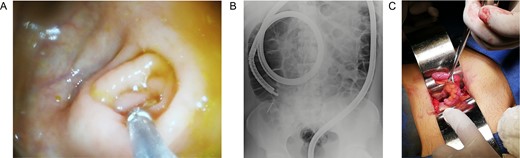

Patient is a 27-year-old male without past medical history. During his annual routine medical examination, an abdominal X-ray was requested. A metallic foreign body (30 mm nail) was discovered in his lower right abdomen (Fig. 1A). With these findings, he was transferred to our hospital. On arrival, he was completely asymptomatic, and he had no recollection of having swallowed the nail. Abdominal examination was unremarkable, and he had no evidence of any surgical scars. With these findings, a contrast-enhanced abdominal computed tomography (CT) revealed the presence of a 30 mm metal nail inside his appendix (Fig. 2A). The appendix had an outer diameter of 5 mm and was surrounded by homogeneous, non-inflamed fat and contained intraluminal air (Fig. 3A). A colonoscopy was requested to assess the cecum to try to remove the foreign body, however, after reaching the cecum and the appendix the nail could not be found (Fig. 1B). An intraoperative abdominal x-ray was needed, which confirmed the presence of the nail in the appendix (Fig. 2B).

(A) Abdominal X-ray with a radiopaque metallic foreign body. (B) Abdominal CT, the metallic foreign body is lodged in the appendix. (C) Abdominal CT, the appendix is surrounded by homogeneous non-inflamed fat and contains intraluminal air.

(A) Colonoscopy, the appendiceal orifice is seen without the foreign object. (B) Intraoperative abdominal x-ray confirming the presence of the nail in the appendix. (C) Appendix during surgery.

In this context, a surgical approach was needed to assess the appendix and the cecum wall. After a Rocky-Davis incision, the appendix was exposed and an object of hard consistency was found at its tip (Fig. 3B). The surgical decision was straightforward, the appendix was resected, and the surgery was completed without complications (Fig. 1C).